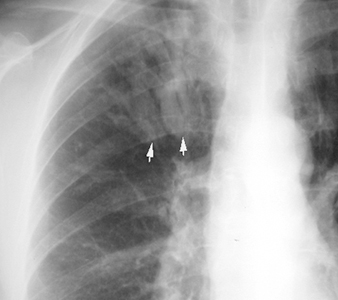

Bronchial Cast

"Gloved finger" appearance. Branching density.